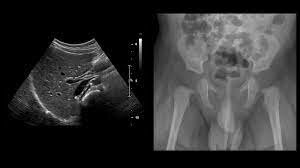

Aparece la tecnica doppler la cual estudia las carótidas

Evento 2 Aplicaciones desde 1895 hasta nuestros días de la radiación ionizante

La tomografia en una herramienta diagnostica de imagenologia